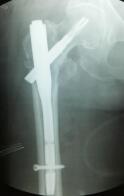

照片顯示骨折位置 運(yùn)用內(nèi)固定手術(shù)后

微創(chuàng)切口+“半瓶墨水”出血量,手術(shù)臺(tái)上,患者為醫(yī)生“點(diǎn)贊” 當(dāng)天下午,在醫(yī)院麻醉科等科室的高效配合下,由吳東海主刀,為老人實(shí)施微創(chuàng)下的右股骨粗隆間骨折閉合復(fù)位PFNA(股骨髓內(nèi)釘)內(nèi)固定術(shù)。

術(shù)中,在X線機(jī)透視下,手法準(zhǔn)確復(fù)位——切開幾個(gè)小口植入PFNA——將骨折固定穩(wěn)定——縫合切口。這一系列動(dòng)作一氣呵成,手術(shù)僅用時(shí)20分鐘,手術(shù)切口總共5針,出血量很少,僅有差不多半瓶墨水的出血量,全過程只有輕微注射穿刺的疼痛。醫(yī)生高效、精準(zhǔn)的手法,贏得了患者的稱贊。在手術(shù)結(jié)束時(shí),薛大爺豎起雙手大拇指為醫(yī)生的精湛技藝比贊,醫(yī)生也為樂觀、勇敢的薛大爺比贊。這一幕溫情默默地流淌在手術(shù)間,讓原本讓人覺得冰冷的手術(shù)間不再冰冷。